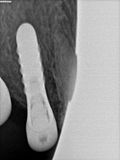

fredlibc | all galleries >> Galleries >> JLin - 15 16 implants > R5.jpg

R5.jpg